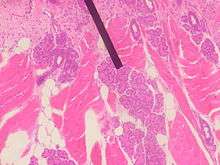

Human Von Ebner's Gland.

Von Ebner's glands, also called Ebner's glands or gustatory glands, are exocrine glands found in the mouth. More specifically, they are serous salivary glands which reside adjacent to the moats surrounding the circumvallate and foliate papillae just anterior to the posterior third of the tongue, anterior to the terminal sulcus.

Von Ebner's glands secrete lingual lipase,[1] beginning the process of lipid hydrolysis in the mouth. These glands empty their serous secretion into the base of the moats around the foliate and circumvallate papillae. This secretion presumably flushes material from the moat to enable the taste buds to respond rapidly to changing stimuli.